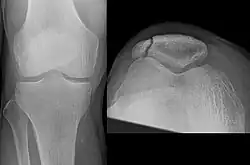

The patella can break in various ways depending on the way it is injured, and into two or more pieces.[1] Types include transverse, the most common, with one fracture line;[5] marginal; osteochondral; and the rare vertical type, or stellate, where a direct compression force gives rise to a comminuted pattern.[5][7] Patella fractures can be further classified as displaced, where the broken ends of bone do not line up correctly and separate by more than 2mm, or undisplaced and stable where pieces of bone remain in contact with each other.[1][7] If fragments of patella bone stick out from the skin it is known as an open patella fracture, and closed if the overlying skin is intact.[1]

Osteochondral fracture of patella -

Vertical patella fracture